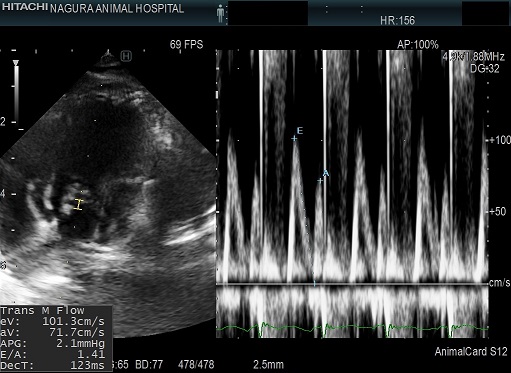

僧帽弁閉鎖不全症は米国獣医内科学会(ACVIM)によって病態によるステージ分け(ステージA~D)がされており、そのステージよって推奨されている治療をガイドラインとし、基本的な治療を行っています。また、個々で異なる病態の変化や新しい知見なども出てくるため、それらを総合的に判断して治療を進めていきます。

ステージの分類は、心臓エコー検査、レントゲン検査、血液検査などを行い、総合的に判断します。

基本的に重症度は心臓エコー検査により判断します。心房の大きさ、左室流出路の血流の速さ、左心室内腔の大きさ、三尖弁逆流や肺高血圧などの有無を確認し、薬の選択をします。お薬の投薬で安定していれば良いですが、発咳や呼吸促拍などがあり落ち着かない状態の場合は、こまめに検査をする必要があります。ただし、検査の際に暴れてしまったり、落ち着いて検査が受けられない子の場合には、検査も負担になりますので簡易的にチェックするのみとなる場合もあります。